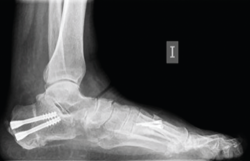

La OPC se realiza bajo anestesia general o regional junto con un bloqueo nervioso anestésico. Se debe tener en cuenta que este procedimiento es tan solo una parte de un conjunto de gestos quirúrgicos destinados a corregir la deformidad, fundamentalmente del pie cavo o pie plano (Figura 1).

Figura 1. Radiografía en carga prequirúrgica.

Los procedimientos que acompañan a la OCP en la corrección de las deformidades suelen marcar el tiempo de descarga e inmovilización. Cuando la osteotomía es el único procedimiento óseo de la corrección, se autoriza una carga protegida con bota de tipo Walker e inicio de ejercicios de flexoextensión de tobillo a las 4-5 semanas, para posteriormente iniciar progresivamente la carga completa 2 semanas después (Figuras 10 y 11).